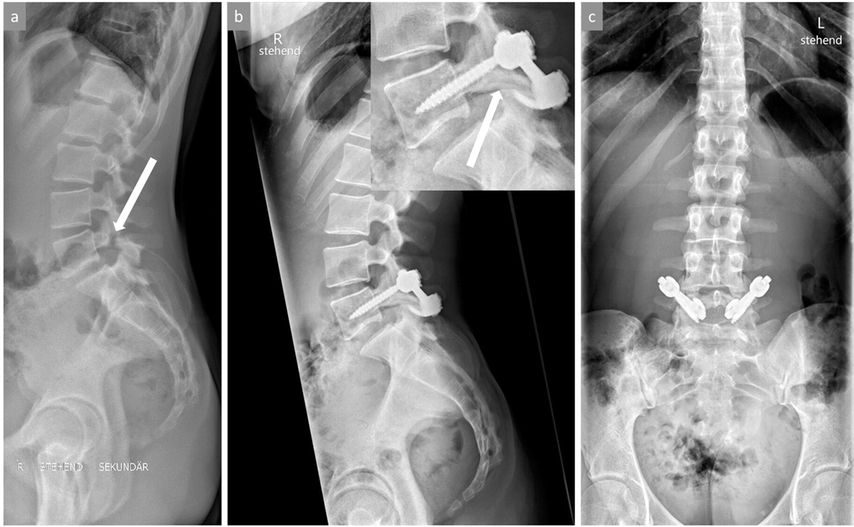

Wenn eine knöcherne Ausheilung der Spondylolyse bei symptomatischen Patienten sehr unwahrscheinlich ist (radiologisch sklerosierte, abgerundete Frakturränder des Pars-Defekts) und insbesondere bei gleichzeitigem Vorliegen einer leichtgradigen Spondylolisthese sind die Ergebnisse konservativer Massnahmen deutlich seltener nachhaltig erfolgreich und ein früheres operatives Vorgehen sollte zumindest angesprochen werden. Bei objektivierbarer Progression der Spondylolisthese und/oder neurologischen Symptomen ist die Indikation für eine operative Stabilisierung grundsätzlich gegeben. Bei fehlenden knöchern-dysplastischen Veränderungen und noch intakter Bandscheibe zwischen den betroffenen Wirbeln (i.d.R. L5/S1) kann ein sogenannter «direct pars repair» durchgeführt werden. Hierbei wird nach Resektion einer allfälligen Pseudarthrose der Defekt mit einer Schraube durch die Pars interarticularis direkt verschraubt oder alternativ ein Konstrukt aus Pedikelschraube und Laminahaken frakturüberbrückend bilateral eingebracht (Abb. 4). Wenn die Betroffenen nicht für einen «direct pars repair» qualifizieren, wird eine (instrumentierte) posterolaterale Fusion der betroffenen Segmente durchgeführt.

Abb. 4: Bild (a) zeigt ein stehendes seitliches Röntgenbild der LWS mit objektivierbarer isthmischer Spondylolyse (Pfeil) im Bereich der Pars interarticularis von LWK5 mit belgeitender leichtgradiger Spondylolisthese LWK5/SWK1. Bilder (b) und (c) zeigen die Situation nach erfolgter Operation mittels «direct pars repair», bei welcher der Pars-Defekt auf beiden Seiten durch ein Pedikelschrauben-Laminahaken-Konstrukt nach Resektion der Pseudarthrosezone überbrückt wird. Der weisse Pfeil im kleinen Bildausschnitt von Bild (b) zeigt eine vollständige knöcherne Ausheilung des ehemaligen Pars-Defekts

Eine höhergradige Spondylolisthese (≥Gleitgrad III) ist selbst bei fehlenden Beschwerden in aller Regel mit einer relevanten Störung des sagittalen Profils verbunden und sollte aufgrund der durchgehend schlechten Prognosen konservativer Therapieansätze operativ versorgt werden. Primäres Ziel dabei ist die Wiederherstellung der segmentalen Lordose und nicht die vollständige Reposition des Wirbelgleitens (Abb. 5). Das Erreichen einer zirkumferenziellen antero-postero-lateralen («360°») Fusion ist mit besseren Langzeitresultaten verbunden als alleinige anteriore oder posteriore Stabilisierungen.17

Abb. 5: Bild (a) zeigt eine hochgradige Spondylolisthese LWK5/SWK1 mit resultierender Kyphosierung in diesem Bewegungssegment. Bilder (b) und (c) zeigen die Situation nach erfolgter Operation mit partieller Reposition des Wirbelgleitens und Wiederherstellung der segmentalen Lordose mittels dorsaler Instrumentierung und ventralen Cages für eine zirkumferenzielle knöcherne Fusion